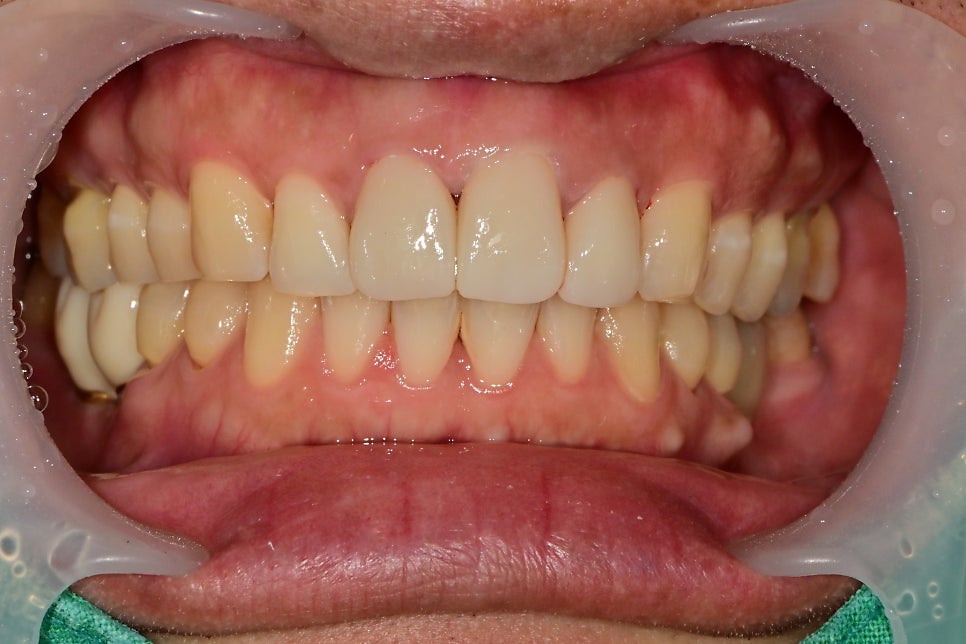

최종 심미보철물의 세팅 날입니다.

전과 비교해서 모양이나 색상이 자연스러워진 것을 볼 수 있습니다.

기존 치아의 색상이 약간 어두운 경우

미백을 추가적으로 하면 더 좋은 효과를 볼 수 있습니다.